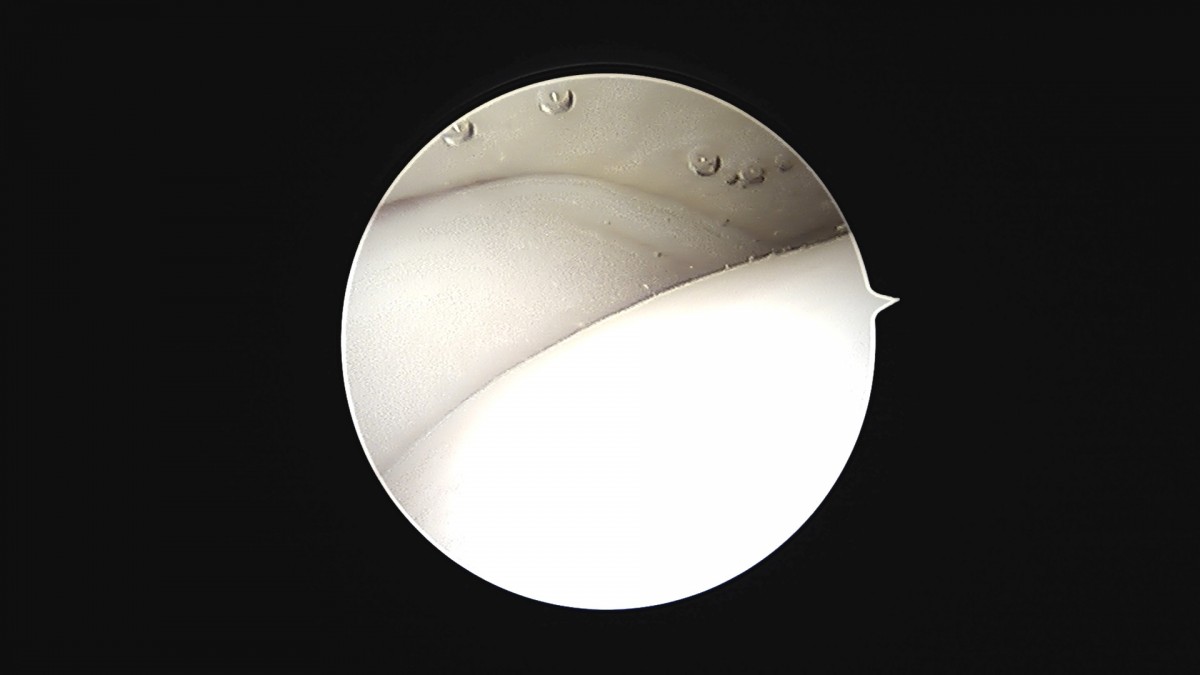

이재상원장님 발목 활액막 절제술 및 인대 봉합술 신진O 환자

작성자 최고관리자 댓글 0건 조회 790회 작성일 25-09-16 15:22